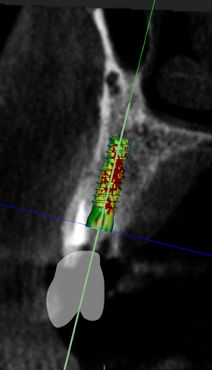

(12.) Postoperative CBCT image of actual implant placement at site No. 21.

Figure 12

(13.) Postoperative CBCT image of actual implant placement at site No. 19.

Figure 13

A healthy 60-year-old female presented for an emergency evaluation because she was experiencing pain associated with tooth No. 20. It was mobile, malposed, and given a diagnosis of irreversible pulpitis. In addition, teeth Nos. 19 and 21 had been missing for more than 5 years. After the evaluation, a discussion revealed that the patient desired implant reconstruction of the lower left quadrant. During this initial visit, a CBCT scan was obtained, and the virtual restoration-driven implant planning was completed, confirming that extraction of tooth No. 20 with robot-assisted immediate implant placement at the sites of teeth Nos. 19 and 21 was a viable option (Figure 9 through Figure 13). Splint placement, CBCT capture of the fiducial array, calibration, and landmark confirmation were completed as described in the first case report. Following the administration of intravenous sedation and local anesthesia, tooth No. 20 was atraumatically extracted. Flap access was obtained from the site of tooth No. 18 to the site of tooth No. 22, and robot-assisted surgical implant placement was completed at the sites of teeth Nos. 19 and 21. Intraoperatively, guide pins were placed to evaluate the position of the proposed osteotomies, and it was determined that both implants should be tilted buccally by 0.4 mm. The necessary changes were made in the software application, and the new implant placement plan was immediately ready for robotic implementation. The implants were robotically delivered to their planned positions at the sites of teeth Nos. 19 and 21 and torqued to initial stability at 50 Ncm and 45 Ncm, respectively (Figure 14 and Figure 15). Healing abutments were placed, and the tissue was closed primarily. In this case, robotic assistance facilitated the performance of surgery on the same day that the patient initially presented and permitted intraoperative modifications to be made.